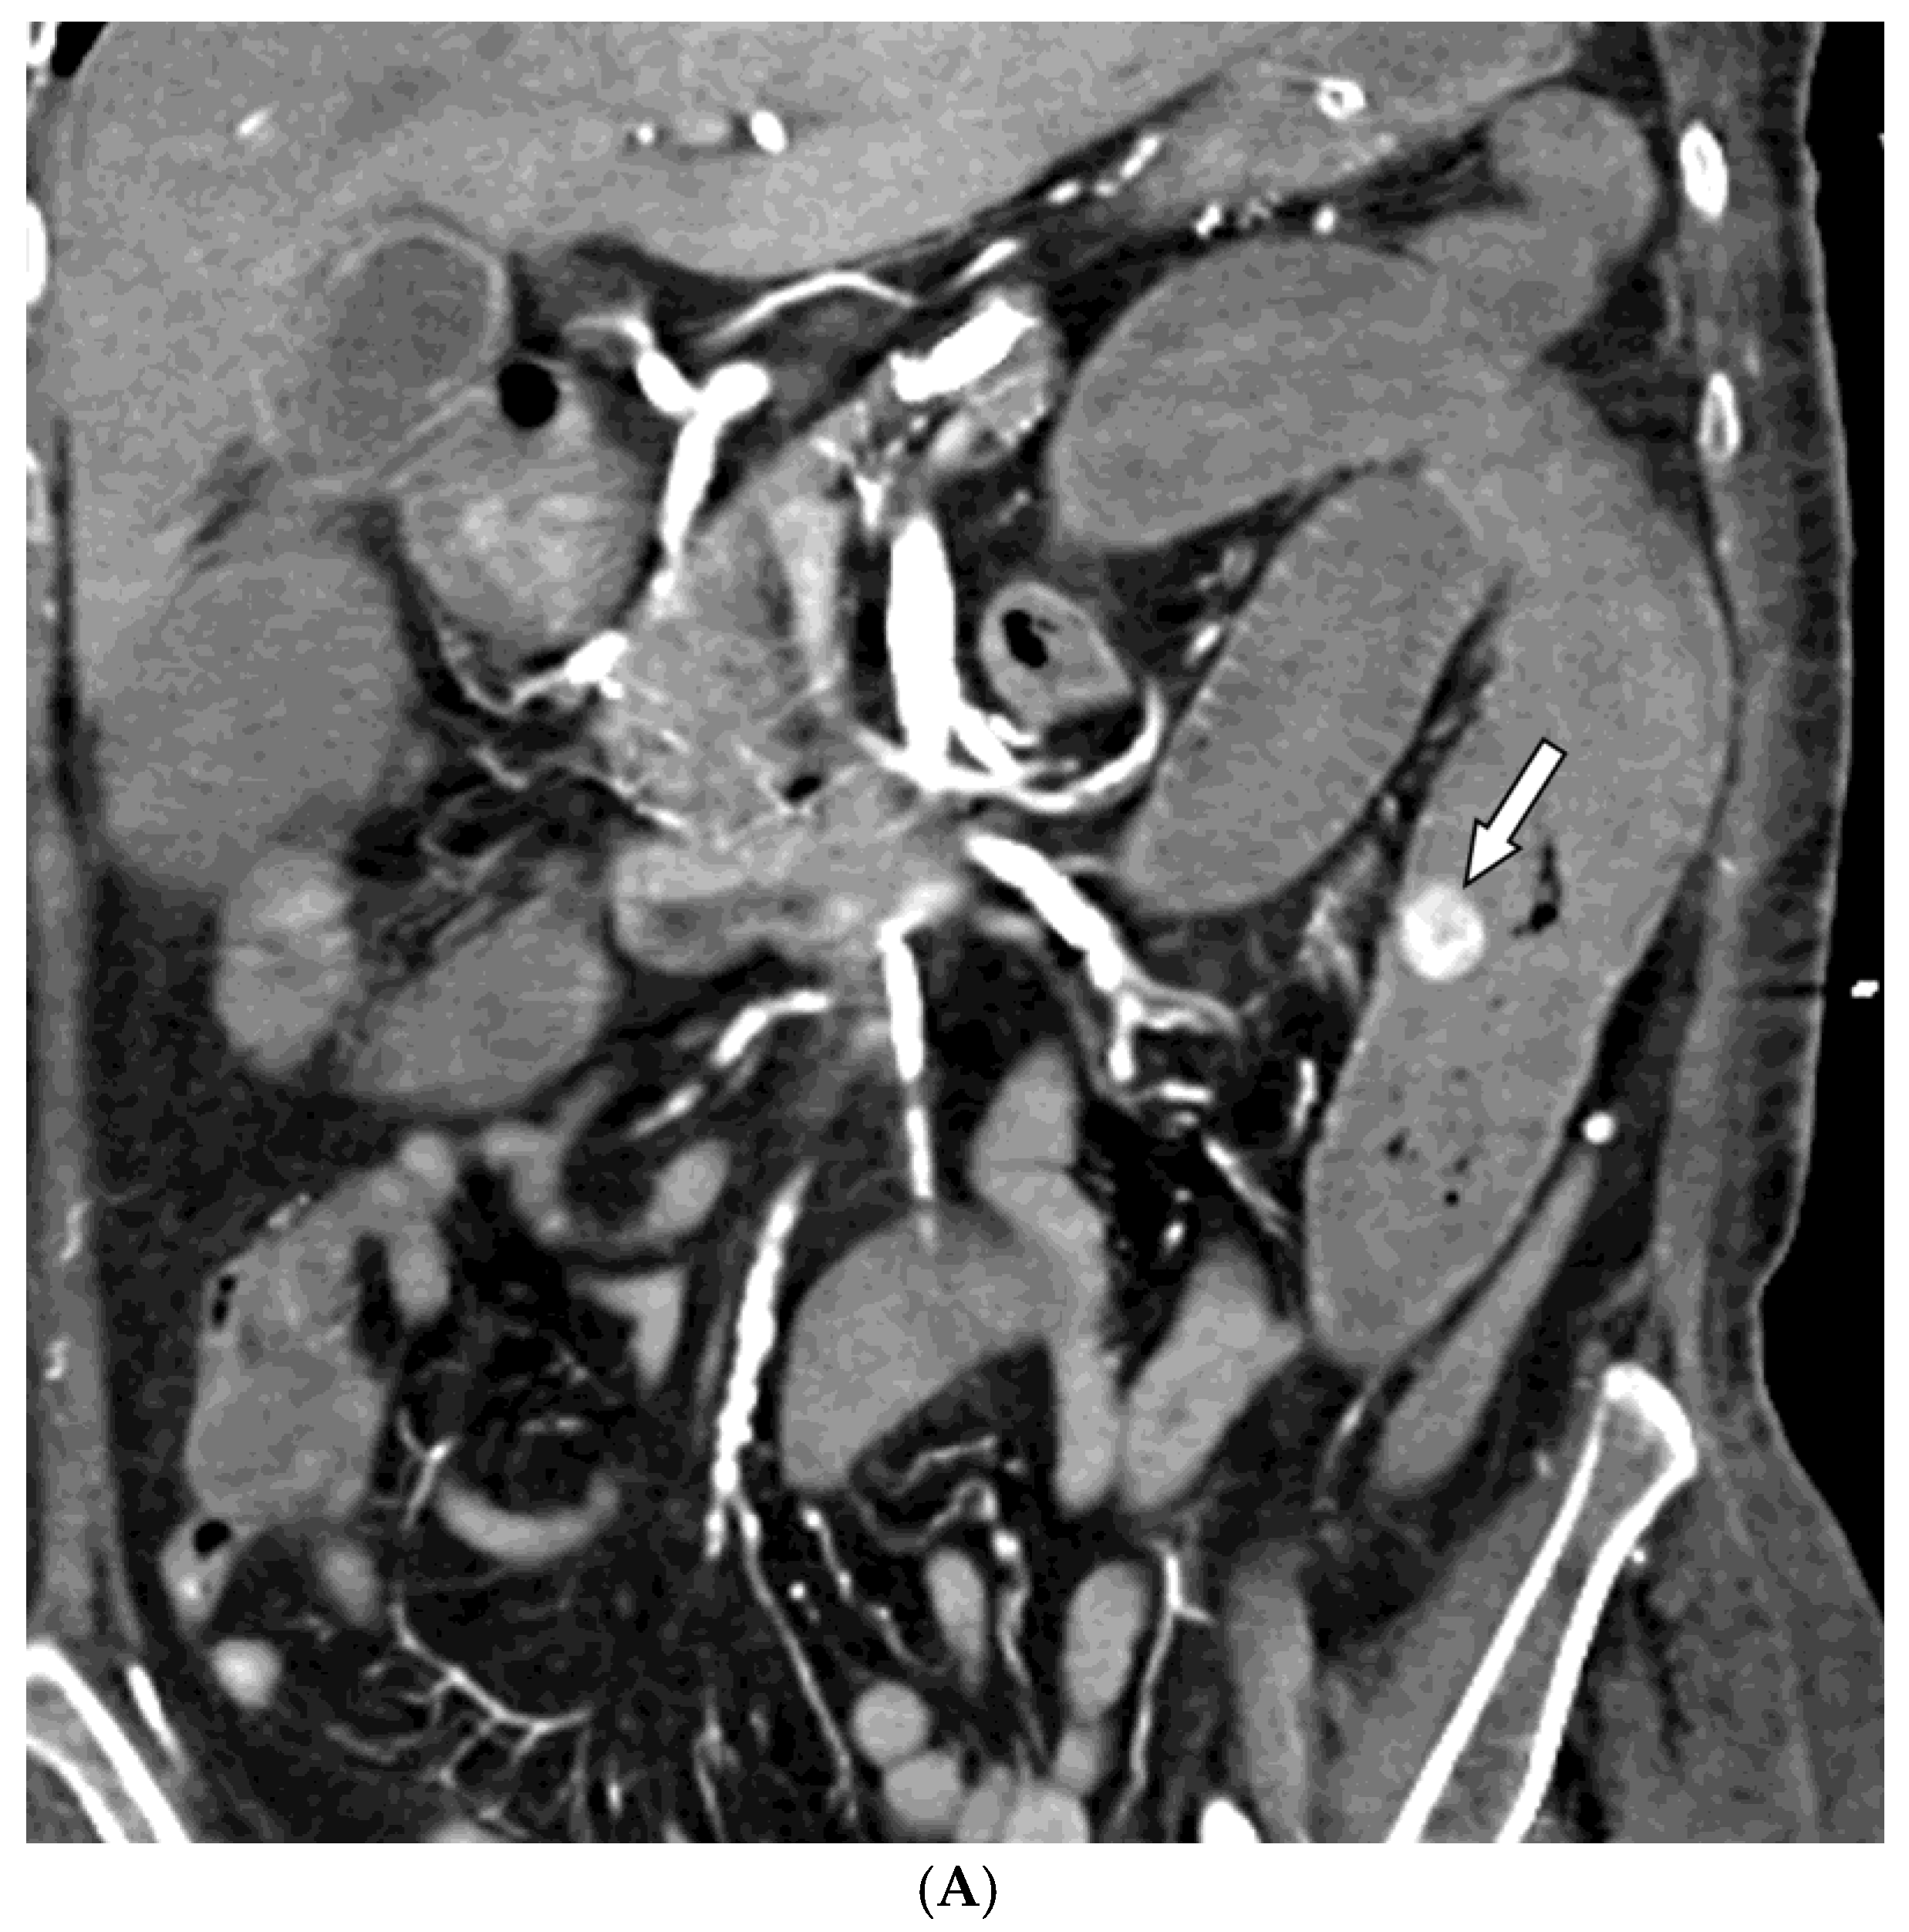

Figure 2. A 67-year-old woman presented with hematochezia. (A) Contrast-enhanced coronal CT image shows luminal contrast extravasation (arrow) at the jejunal loop. (B) Selective jejunal arteriography shows contrast extravasation (arrow). (C) Several levels of the vasa recta (arrows) were embolized with quick-soluble gelatin sponge particles (150–350 µm). (D) Post-embolization arteriography shows devascularization of the previously embolized vasa recta. No further bleeding occurred before the patient’s death one month after embolization.